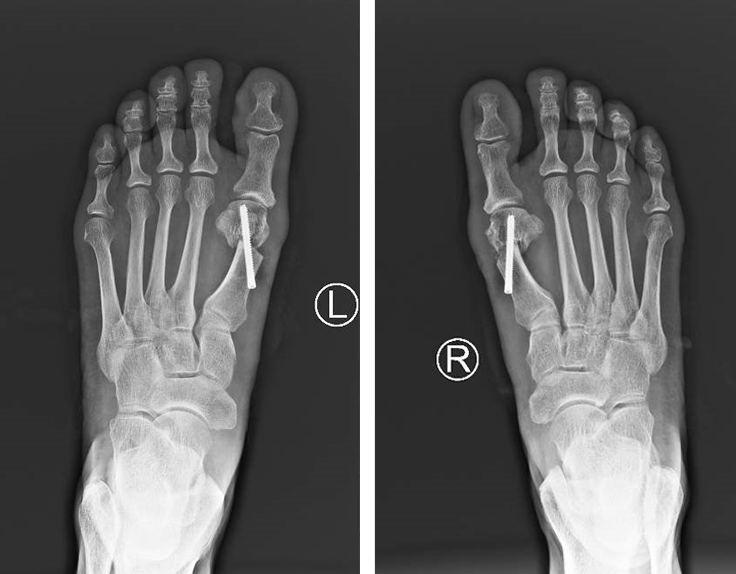

完善的术前检查后,石院长徐主任魏笛医生团队给患者进行了双足踇外翻截骨矫形内固定+拇收肌松解手术。术中,C型臂定位后,手术医生先后于右足及左足第1跖趾关节近端内侧做一1cm切口,采用低频超声骨刀微创截骨,向外侧轻推跖骨头端,以螺钉内固定,术中出血仅20毫升。老人及家属对手术效果很满意。